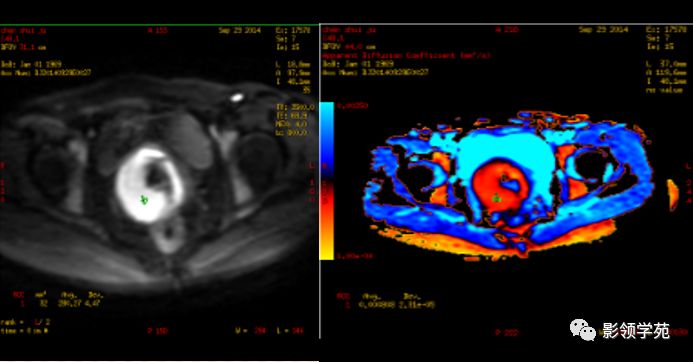

磁共振扩散加权成像,DWI

DWI是目前唯一能在活体观察组织水分子微观运动的无创性影像学方法,可以检测出与组织含水量变化相关的形态学和生理学早期改变,并以表观扩散系数(ADC)值来量化表示。

DWI:局限性高信号,癌组织ADC值<癌旁组织<小于正常宫颈组织

宫颈癌术后复发患者,DWI上病灶较T2 fs及T1+C更加明显